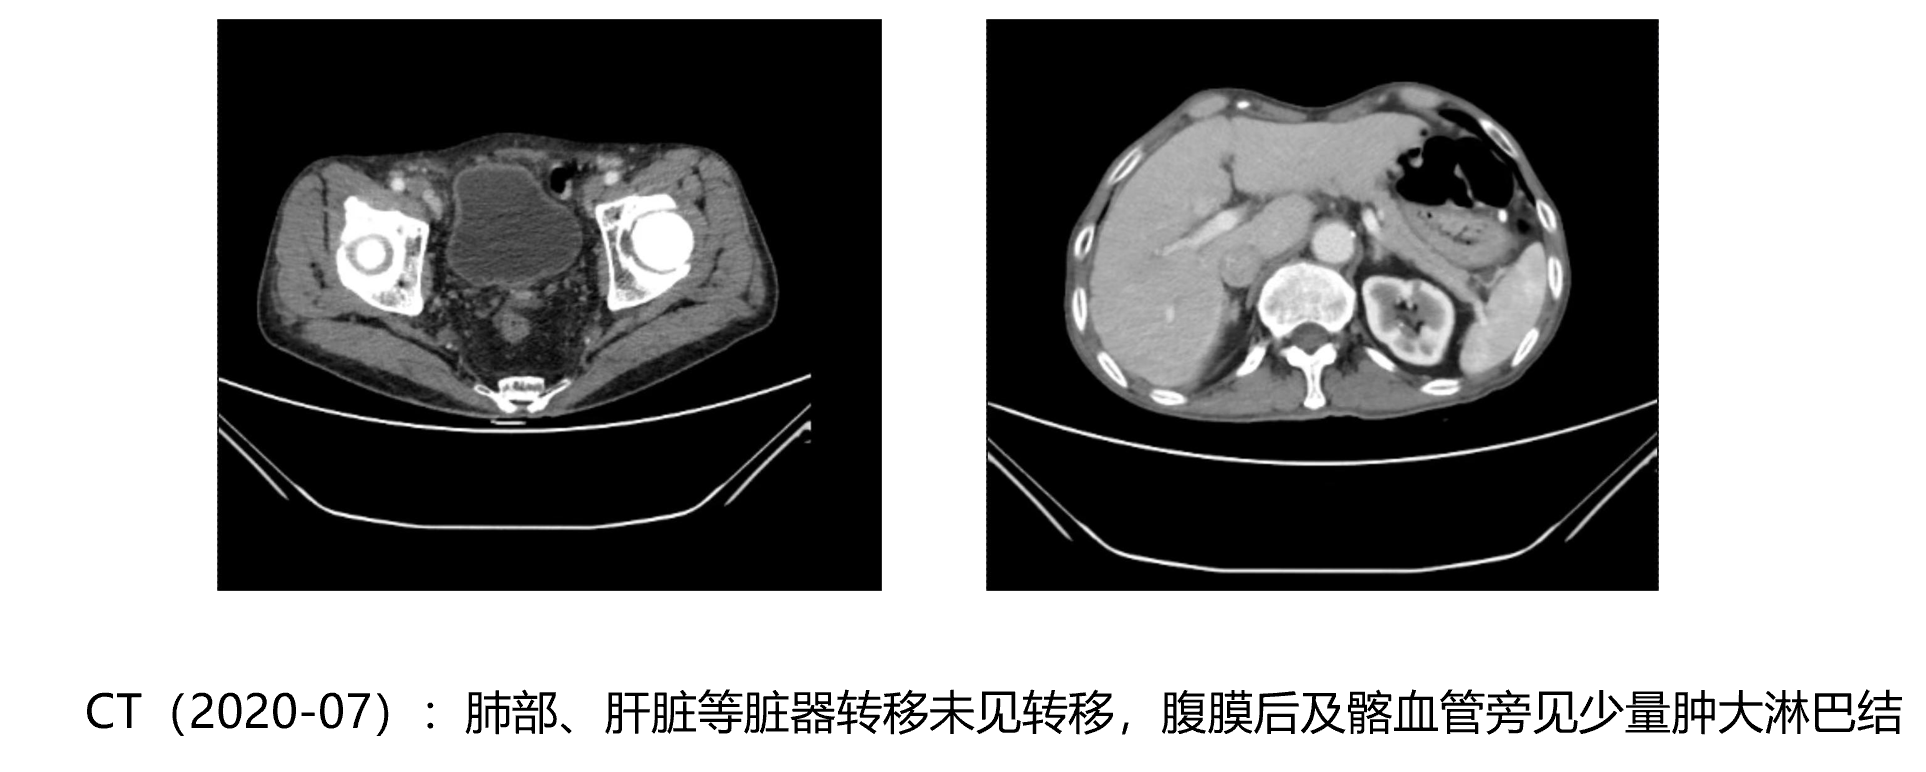

• CT(2020-07):肺部、肝脏等脏器转移未见转移,腹膜后及髂血管旁见少量肿大淋巴结

治疗方案

• 2020年8月:ADT治疗:亮丙瑞林(3.75mg 皮下注射)

• 2020年12月-2021年8月: 亮丙瑞林+阿比特龙+泼尼松+唑来膦酸